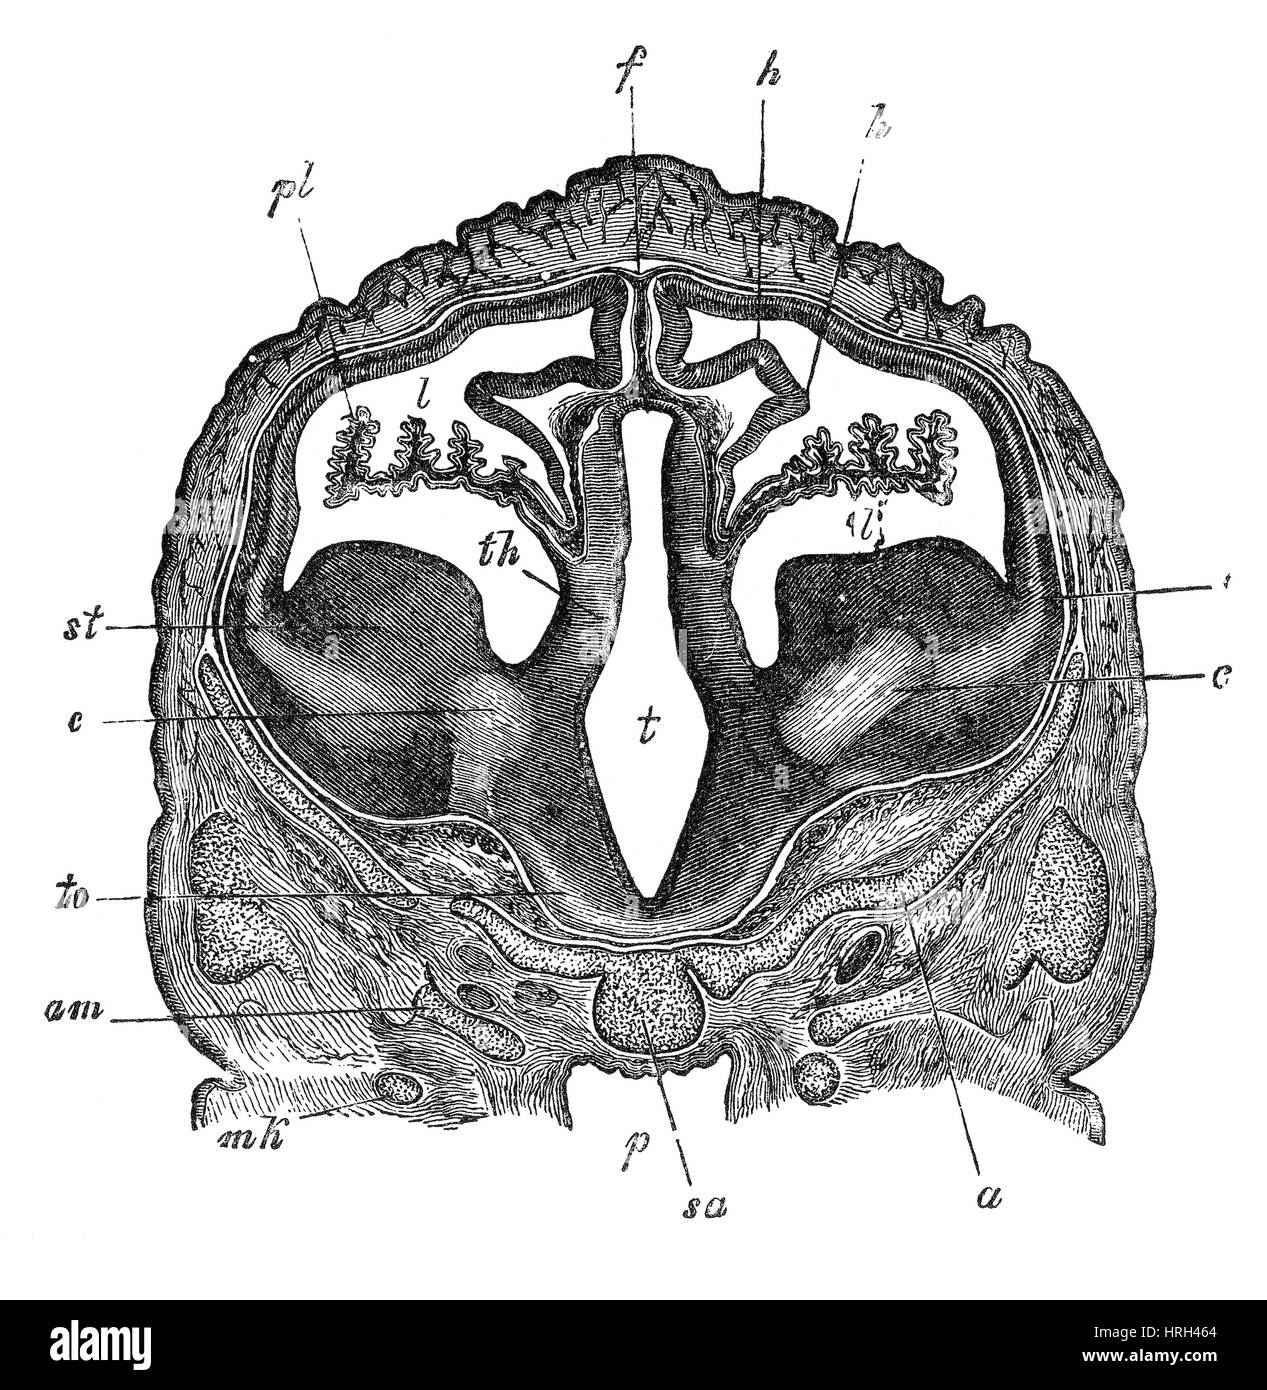

RF3CN8WHW–Darstellung der vergrößerten lateralen und dritten Ventrikel des Gehirns (Hydrozephalus), hervorgerufen durch einen Hirntumor, der den Aquädukt des Gehirns komprimiert.

RM2ANEPH2–Die encyclopdia Britannica; ein Wörterbuch der Künste, Wissenschaften, Literatur und allgemeinen Informationen. Trakt. Der dritten Ventrikel (siehe Abb. 6) isa Hohlraum im mesialplane zwischen den beiden Optic thalami gelegen. Sein Dach ist durch die veluminterpositum und Körper der fornix gebildet; der Fußboden durch die posteriorperforated Raum, Korpora ajbicantia, Tuber cinereum, infundibulum und Optic commissure; seine vordere Begrenzung durch die anteriorpillars Der fornix, anterior Commissure und lamina cinerea; itsposterior Begrenzung durch den Corpora quadrigemina und posteriorcommissure. Den Hohlraum der Ventrikel ist o

RF3CN8WHP–Illustration des vergrößerten lateralen und dritten Ventrikels des Gehirns (Hydrozephalus), hervorgerufen durch einen Hirntumor, der den Aquädukt des Gehirns komprimiert.